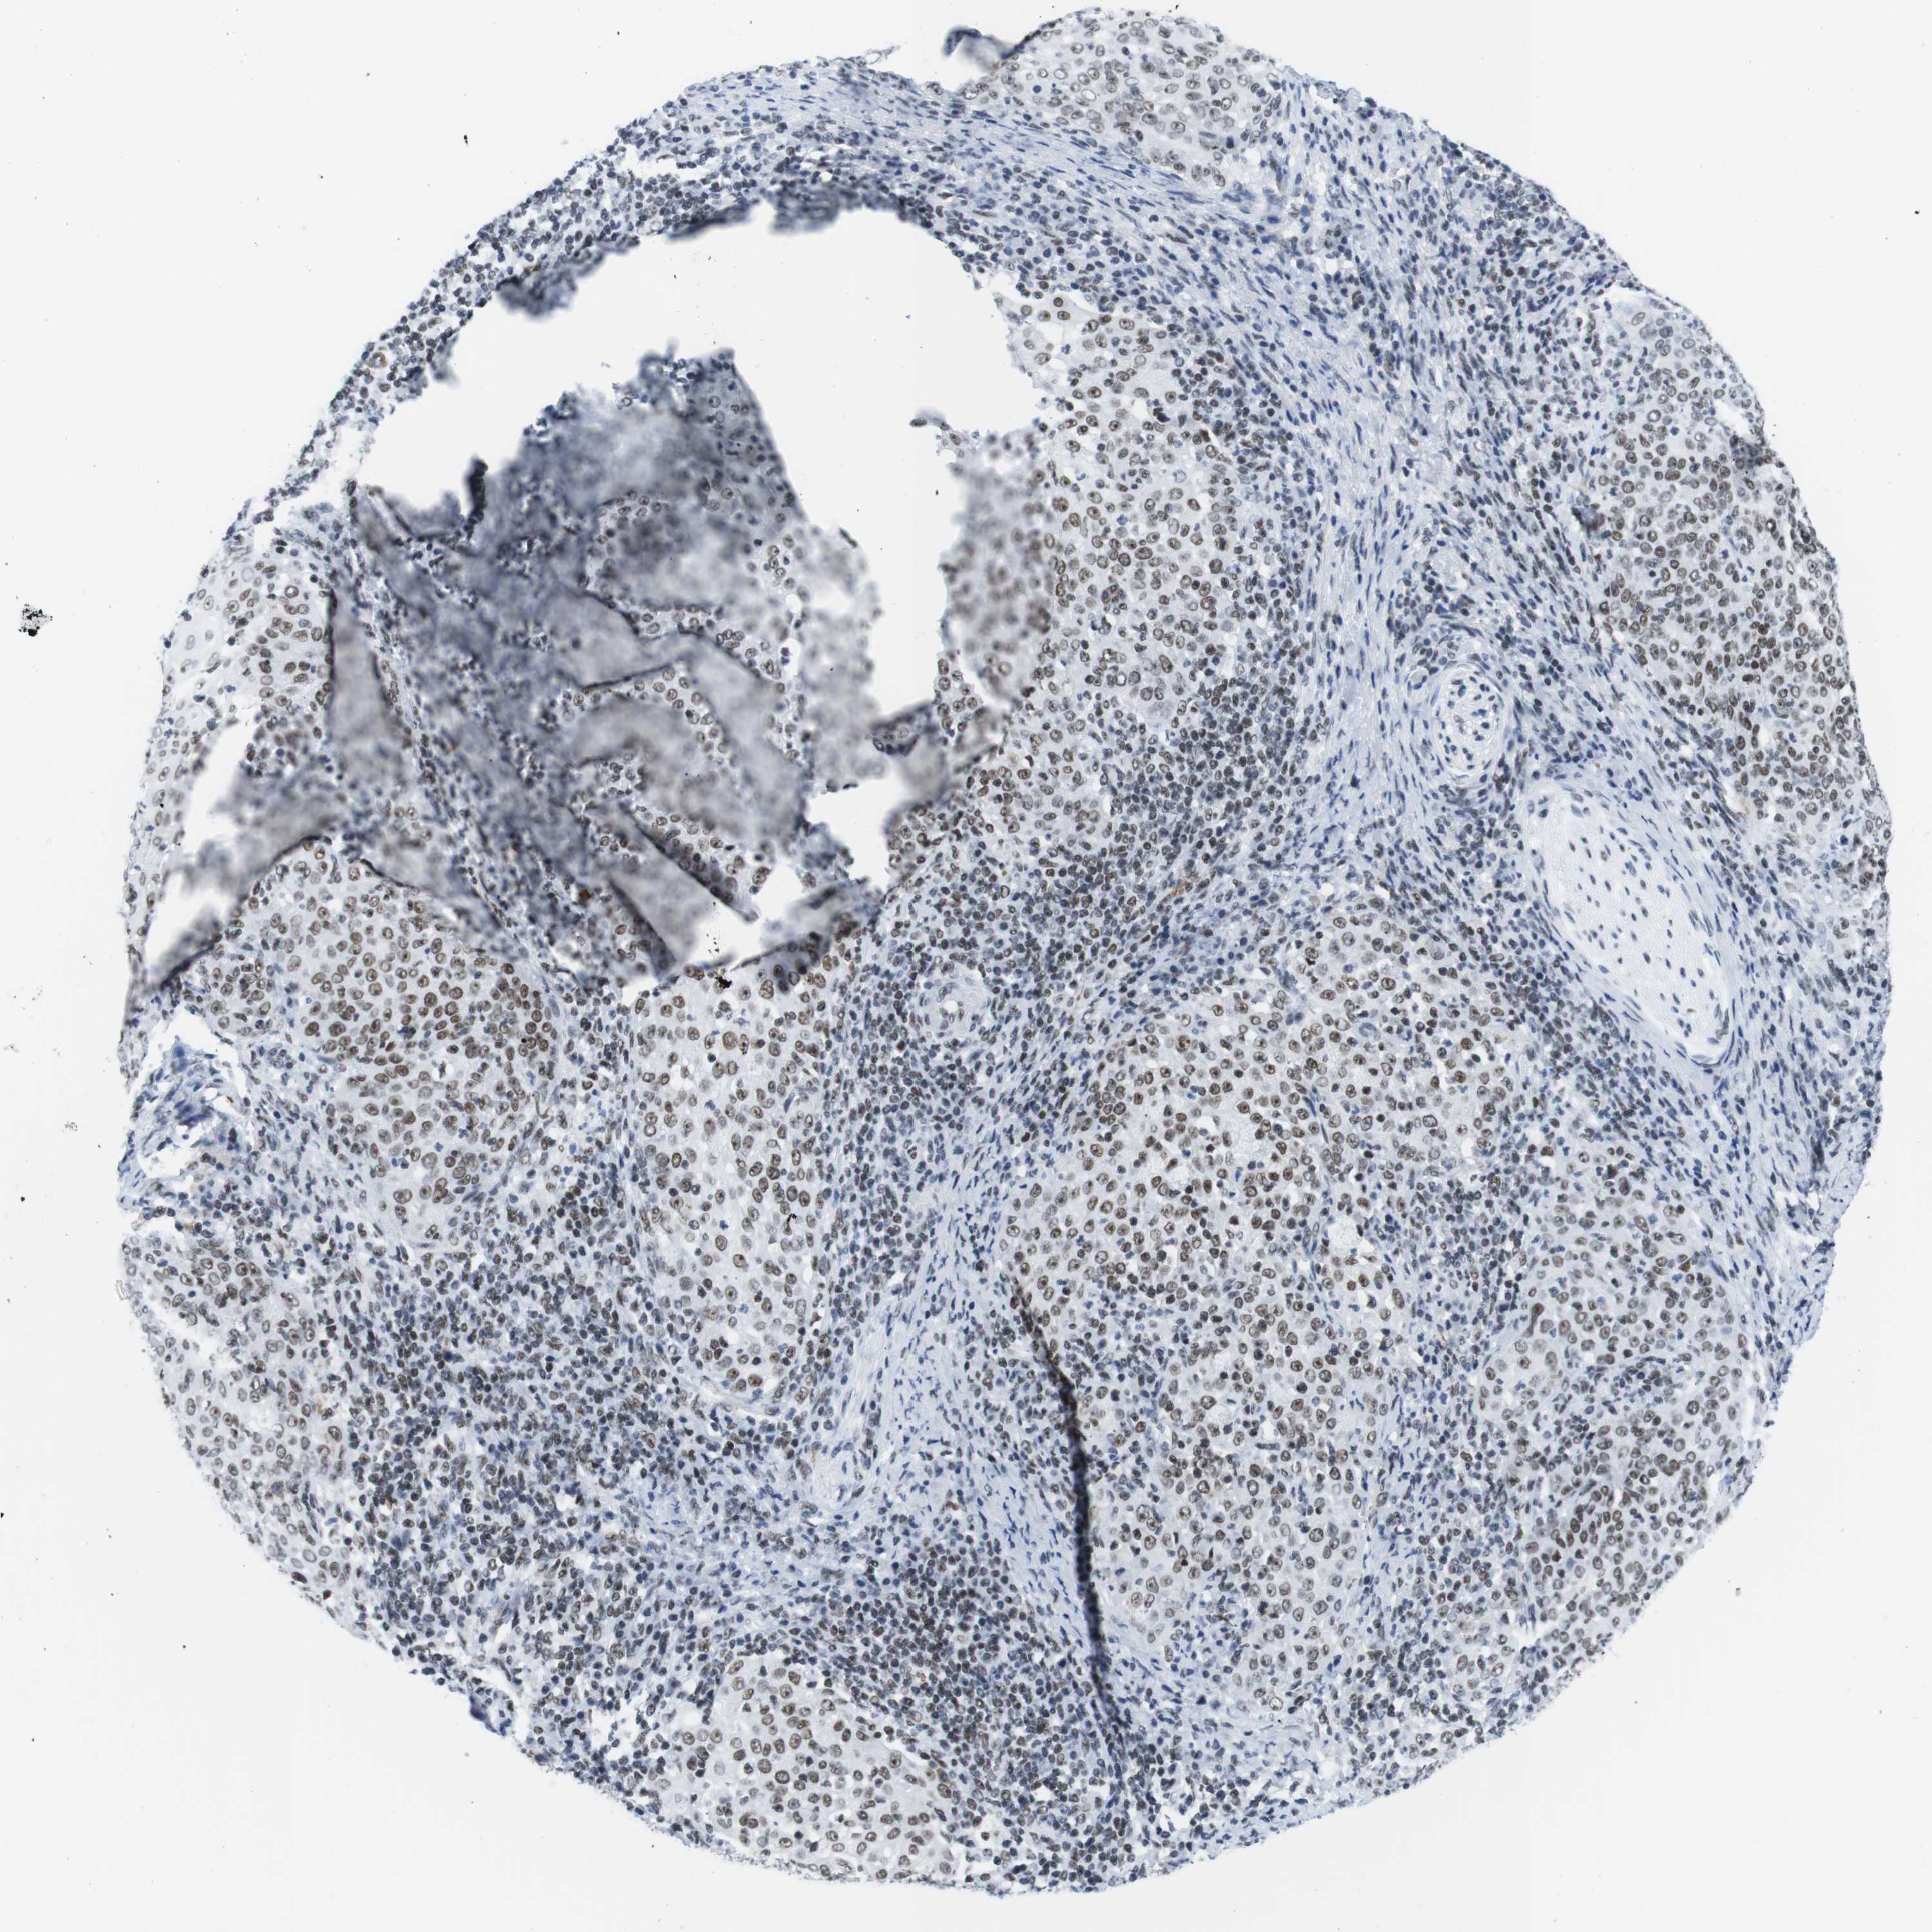

CERVICAL CANCER - Protein expressioni

A mouse-over function shows sample information and annotation data. Click on an image to view it in a full screen mode. Samples can be filtered based on level of antibody staining by selecting one or several of the following categories: high, medium, low and not detected. The assay and annotation is described here.

Note that samples used for immunohistochemistry by the Human Protein Atlas do not correspond to samples in the TCGA dataset.

Antibody stainingi

Antibody staining in the annotated cell types in the current human tissue is reported as not detected, low, medium, or high, based on conventional immunohistochemistry profiling in selected tissues. This score is based on the combination of the staining intensity and fraction of stained cells.

Each image is clickable and will lead to virtual microscopy that enables deeper exploration of all samples and also displays staining intensity scores, fraction scores and subcellular localization as well as patient and tissue information for each sample.

Antibody HPA002134

Antibody CAB016293

Staining

High

Medium

Low

Not detected

Intensity

Strong

Moderate

Weak

Negative

Quantity

>75%

75%-25%

<25%

None

Location

Nuclear

Cytoplasmic/membranous

Cytoplasmic/membranous,nuclear

Squamous cell carcinoma, NOS

Adenocarcinoma, NOS